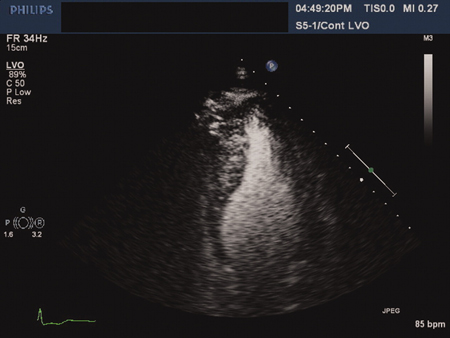

Apical hypertrophic cardiomyopathy: 4-chamber echocardiographic view with contrast

Ahmed I, Smalley SJ, Zhu DWX, et al. Sudden cardiac arrest in apical hypertrophic cardiomyopathy. BMJ Case Reports. 2009;doi:10.1136/bcr.04.2009.17